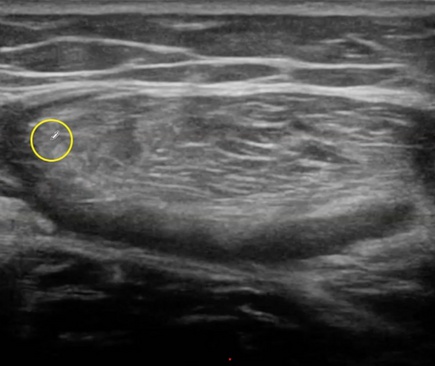

El corte transversal es elprimer corte que debes hacer, te va a permitir ubicarte en el espacio e identificar con mayor rapidez al recto anterior. Su arquitectura es un tanto atípica.

El recto anterior tiene un septo central en forma de S (azul). Las roturas musculares del recto anterior, son frecuentes próximas al septo (aunque tambión podemos encontrarnos roturas miofasciales que tambien te enseñaremos).

El contorno de la sección transversal del recto anterior queda delimitada por el contorno (verde).